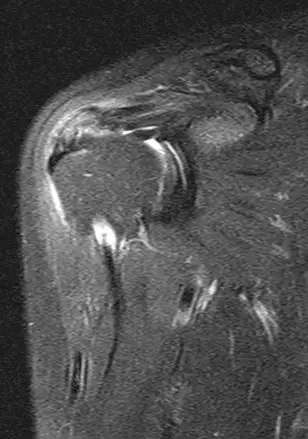

本題提供右肩的 X 光及 MRI 影像各一張:

MRI 影像(圖二): T2 加權 MRI 影像顯示棘上肌腱及 subdeltoid bursa 區域有低訊號(T2 hypointense)病灶,對應鈣化沉積(calcific deposit),周圍可見**高

...(解析預覽)...